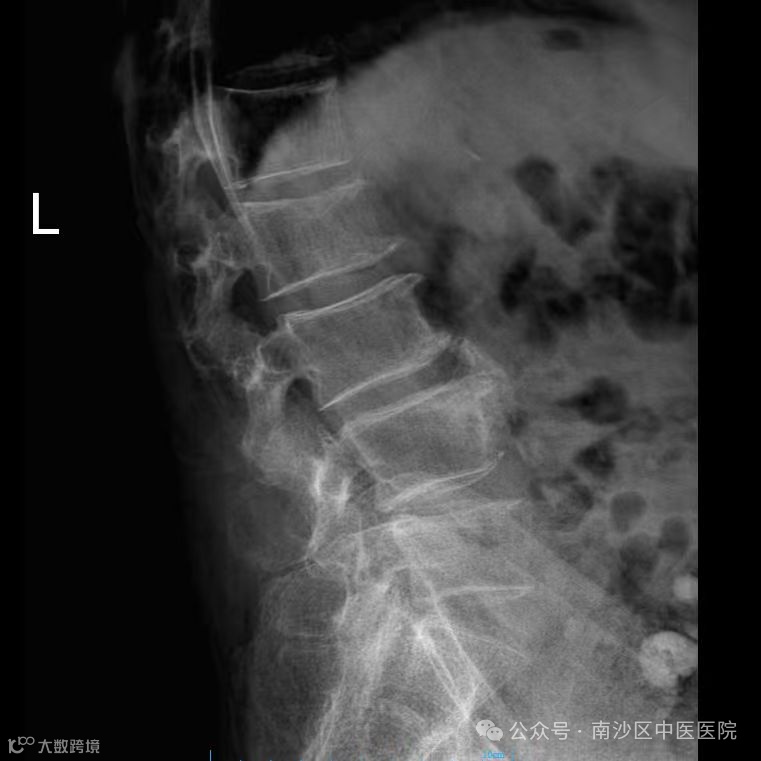

术后

术后当日,张婆婆疼痛显著缓解,第二天即可在辅助下站立,第三日已能扶栏慢步行走。